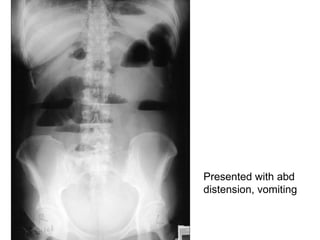

AXR- small bowel obstruction Describe? Ladder pattern of dilated loops Central position Striations complete across width of loops (valvulae conniventes/circular mucosal fold) >3cm <5cm Causes? Luminal: fecal/food, gallstone ileus, pedunculated tumour Intramural: congenital atresia, tumour, Crohn’s dz, diverticulitis Extramural: strangulated hernia, volvulus/intussusception, adhesion/banding 2 S&S? Vomiting Abd pain Abd distension constipation Vs large bowel: Peripheral Haustrations of taenia coli >5cm

Presented with abd distension, vomiting

AXR- intestinal obstruction 3 abnormalities? Dilated bowel Multiple air fluid level (normal <4) Paucity of air distal to obstruction Dx? Intestinal obstruction 2 causes? Adhesion/banding Tumour (pedunculated/intramural)

AXR- small bowelobstruction Describe? Ladder pattern of dilated loops Central position Striations complete across width of loops (valvulae conniventes/circular mucosal fold) >3cm <5cm Causes? Luminal: fecal/food, gallstone ileus, pedunculated tumour Intramural: congenital atresia, tumour, Crohn’s dz, diverticulitis Extramural: strangulated hernia, volvulus/intussusception, adhesion/banding 2 S&S? Vomiting Abd pain Abd distension constipation Vs large bowel: Peripheral Haustrations of taenia coli >5cm

Presented with abddistension, vomiting

AXR- intestinal obstruction3 abnormalities? Dilated bowel Multiple air fluid level (normal <4) Paucity of air distal to obstruction Dx? Intestinal obstruction 2 causes? Adhesion/banding Tumour (pedunculated/intramural)